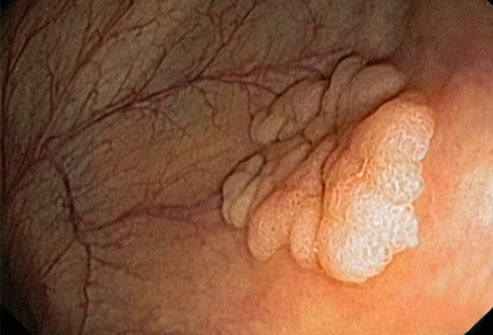

Ung thư đại trực tràng

Đây là nguyên nhân ung thư gây tử vong thứ hai. Đàn ông có nguy cơ mắc ung thư đại trực tràng cao hơn phụ nữ. Đa số các bệnh ung thư đại trực tràng thường phát triển chậm, do sự phát triển bất thường của các polyp ở đại tràng: tăng trưởng trên bề mặt bên trong của ruột. Sau khi ung thư phát triển, nó có thể xâm nhập, hoặc lây lan đến các bộ phận khác của cơ thể. Cách để ngăn ngừa ung thư đại trực tràng là tìm và loại bỏ các polyp ở khu vực đại trực tràng từ khi mới xuẩt hiện, không để chúng phát triển thành ung thư.

Nam giới nên khám đại trực tràng từ 50 tuổi. Nội soi đại trực tràng là một phương pháp đơn giản, nhưng hiệu quả trong việc phát hiện sớm các polyp hoặc ung thư đại trực tràng.